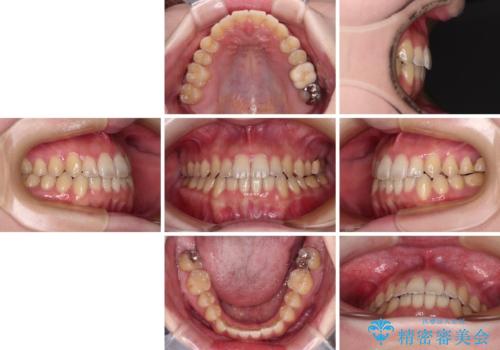

オープンバイトと前歯のデコボコをインビザライン矯正で解消

オープンバイトは舌の突出癖により誘発され、治療後も突出癖が残っている容易に後戻りしてしまいます。

治療期間を短縮するためにも、舌突出癖の改善が極めて重要となります。